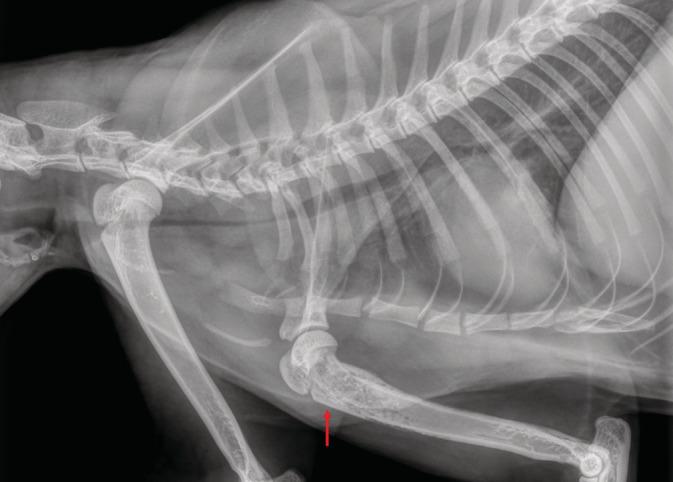

Tracheal intubation (TI) is a common procedure that rarely entails life-threatening complications. A 1.5-year-old female spayed cat presented with acute signs of respiratory distress 5 weeks after undergoing TI. Radiographs revealed a marked, segmental, tracheal narrowing. A hard, 5-cm-long, white-yellowish tissue was identified and removed from the trachea, with subsequent resolution of clinical signs and radiographic changes. Microscopically, the tissue consisted of fibrin and lytic neutrophils, interspaced with optically empty cavities and a few remains of talcum powder and hair shafts. Consequently, a diagnosis of obstructive fibrinous tracheal pseudomembrane (OFTP) was made. A rare complication of TI in humans, OFTP should also be suspected in cats with respiratory distress, a history of TI and radiographic evidence of tracheal narrowing. Based on cases from other species and the cat described herein, the condition can be easily resolved with OFTP removal.